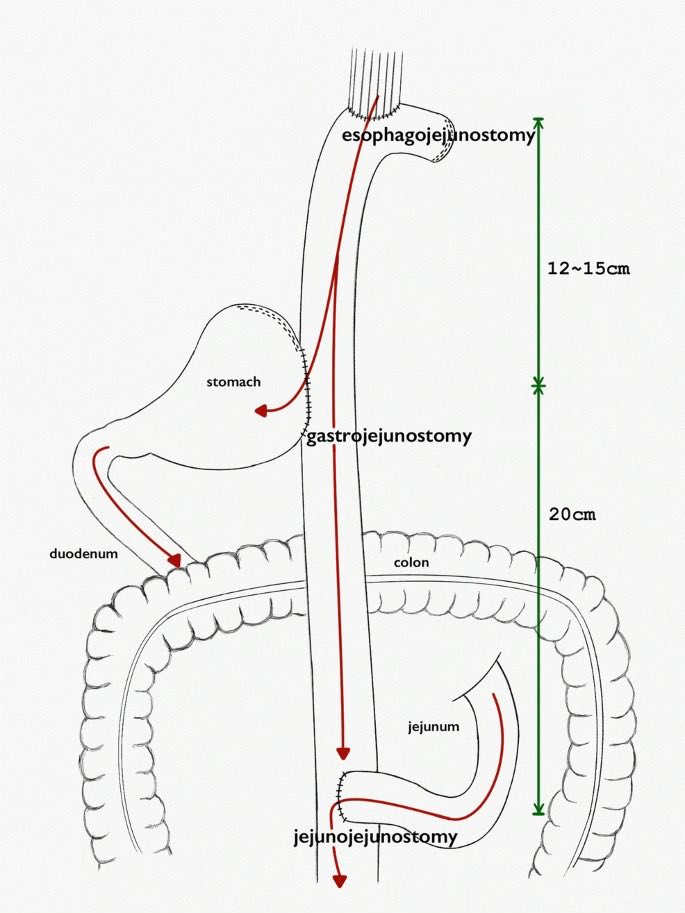

Ung thư dạ dày là một trong những nguyên nhân gây tử vong hàng đầu trên thế giới. Thống kê Globocan 2020 tại Việt Nam, ung thư dạ dày đứng thứ 4 về số lượng ca mắc mới sau ung thư gan, ung thư phổi, ung thư vú. Số lượng ca tử vong đứng thứ 3 sau ung thư gan, ung thư phổi. Điều trị ung thư dạ dày chủ yếu vẫn là phẫu thuật. Cắt dạ dày kèm nạo hạch theo trường phái Nhật Bản đã được chấp nhận rộng rãi ở nhiều nước Châu Á và một số trung tâm ở Châu Âu. Tại Bệnh viện Ung bướu Đà Nẵng, chúng tôi đã áp dụng phẫu thuật nội soi điều trị ung thư dạ dày một cách thường quy trong những trường hợp ung thư giai đoạn sớm. Với những u nhỏ giai đoạn sớm tại vị trí tâm vị thực quản và 1/3 trên dạ dày, thay vì cắt toàn bộ dạ dày, bệnh nhân có thể được điều trị bằng phẫu thuật nội soi cắt phần trên dạ dày và mang lại chất lượng cuộc sống sau mổ tốt hơn. Một bệnh nhân có tiền sử mổ cắt tuyến giáp toàn bộ 3 năm, ung thư nội mạc tử cung đã được phẫu thuật và hoá trị cách đây 6 năm hiện đang ổn định, nội soi dạ dày phát hiện u phình vị kích thước 1.5cm, sinh thiết qua nội soi cho kết quả ung thư tuyến. Đây là một trường hợp ung thư 1/3 trên dạ dày giai đoạn sớm, được chúng tôi áp dụng phương pháp phẫu thuật nội soi hoàn toàn cắt bán phần trên dạ dày kèm nạo hạch, tái lập lưu thông tiêu hóa kiểu “Double-tract” . So với kiểu nối dạ dày – thực quản truyền thống, ưu điểm của kiểu nối “Double-tract” là miệng nối thực quản hỗng tràng không căng, chống trào ngược dạ dày thực quản. Sau mổ bệnh nhân hồi phục tốt, ít đau và xuất viện sau 1 tuần.

Hình 1: Ống tiêu hóa sau khi được tái lập